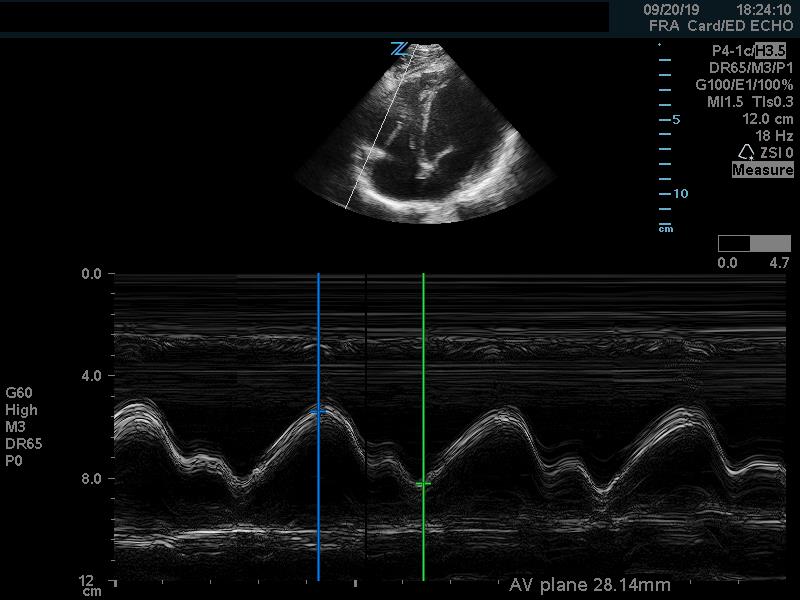

The cardiac component is essential to evaluation of a hypotensive patient as it can provide valuable information about cardiac physiology and etiology of shock. The goal of the cardiac portion of the examination is to classify presence or absence of pericardial effusion, pericardial tamponade, evaluate left and right ventricular contractility and chamber size and thus link these findings to the etiology of shock. Pericardial effusion with tamponade may be identified as a cause of obstructive shock. As fluid and pressure in the pericardial sac increases, early diastolic collapse of the right ventricular free wall is seen. (Video 1) This can be assessed visually in the parasternal long view by placing an M-mode line through the right ventricle (RV) and left ventricle (LV), including the interventricular septum and anterior leaflet of the mitral valve. (Figure 3) This allows for easy identification of right ventricular diastolic collapse, which is indicative of tamponade physiology.

Figure 3. Right ventricular diastolic collapse viewed in M-mode. Note motion of mitral valve leaflet, in the mid-field. Valve opening indicates diastole, which can then be compared to the collapse of the right ventricle in the near field.